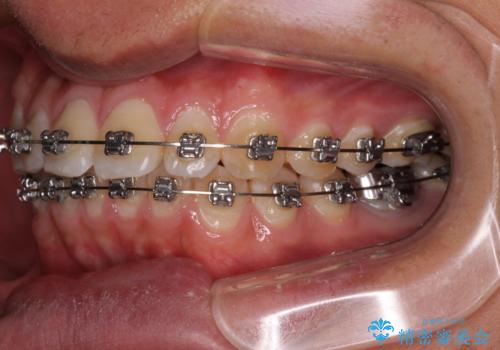

- 矯正装置

- メタルブラケット

- 治療期間

- 1年